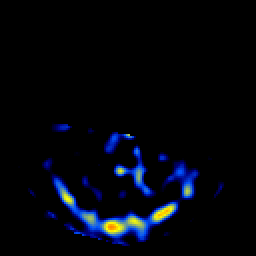

SPECT TL Study #8 -- Slice #13

[Home][Help][Clinical][Tour 1][Tour 2][Tour 3] Slice 13